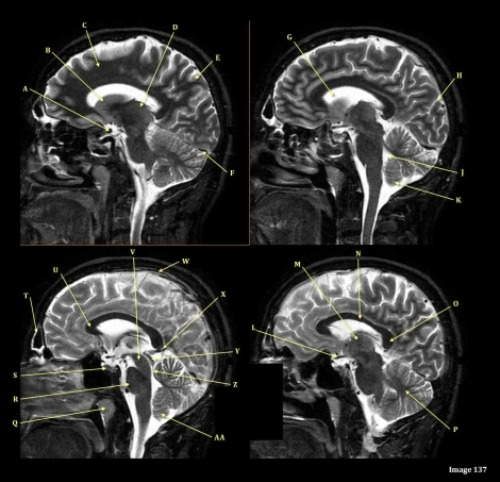

Image 8 is an example of a ____ weighted sequence acquired in the ____ scan plane.

A. T1; Axial

B. T1; Sagittal

C. T2; Axial

D. T2; Sagittal

Letter A in Image 8 is pointing to:

A. Tentorium

B. Corpus callosum

C. Hypothalamus

D. Fourth ventricle

E. Lateral Ventricle

Letter D in Image 8 is pointing to:

B. Cerebellum

C. Thalamus

E. Medulla oblongata

Letter B in Image 8 is pointing to:

Letter E in Image 8 is pointing to:

Letter F in Image 8 is pointing to:

Letter R in Image 137 is pointing to:

A. Pons

B. Cerebral peduncle

D. Caudate nucleus

E. Cerebellum

F. Basal vein